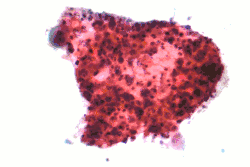

| Micrograph of a squamous carcinoma, a type of non-small-cell lung carcinoma, FNA specimen, Pap stain. | |

Squamous-cell lung carcinoma

Squamous-cell carcinoma (SCC) of the lung is more common in men than in women. It is closely correlated with a history of tobacco smoking, more so than most other types of lung cancer. According to the Nurses' Health Study, the relative risk of SCC is around 5.5, both among those with a previous duration of smoking of 1 to 20 years and those with 20 to 30 years, compared to "never smokers" (lifelong nonsmokers).[13] The relative risk increases to about 16 with a previous smoking duration of 30 to 40 years and roughly 22 with more than 40 years.[13]